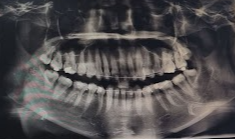

2022/08/16 발치한 자리 사진에 보이는 것이 좌측에 발치한 공간인데요

저번 포스팅에서도 얘기했듯이

생각했던 것 보다 치아 하나가

차지하고 있는 공간이 넓다는 것을 깨달았습니다.

저 사이 공간이 다 닫히고 배열이 완료되어야

비로소 교정이 끝나는 것일 텐데

얼마나 더 긴 시간이 남아있을까요?